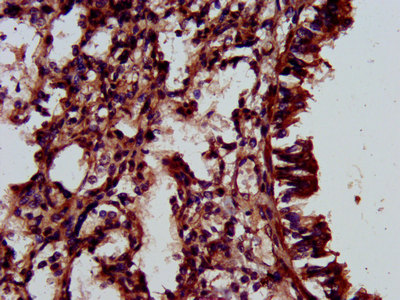

IHC (Immunohiostchemistry)

(IHC image of AAA234673 diluted at 1:500 and staining in paraffin-embedded human lung tissue performed on a Leica BondTM system. After dewaxing and hydration, antigen retrieval was mediated by high pressure in a citrate buffer (pH 6.0). Section was blocked with 10% normal goat serum 30min at RT. Then primary antibody (1% BSA) was incubated at 4 degree C overnight. The primary is detected by a biotinylated secondary antibody and visualized using an HRP conjugated SP system.)